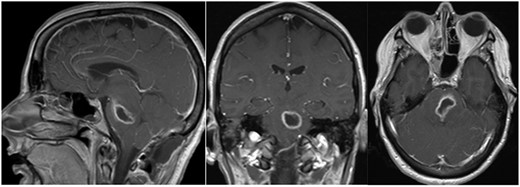

A 44-year-old female presented initially to an outside hospital with difficulty in speaking, right-sided facial droop and difficulty in walking. She also endorsed a 1-week history of intermittent headache. Magnetic resonance imaging (MRI) of brain demonstrated a ring-enhancing pontine lesion with surrounding vasogenic edema consistent with a brainstem abscess measuring 3.6 × 2.4 × 3.7 cm (Fig. 1a–c). There were no areas of ischemia. Pertinent history revealed no dental, cardiac or pulmonary source of infection. She had no history of intravenous drug use.

Pe-op axial, coronal and sagittal T1 post-contrast MRIs demonstrating rim-enhancing pontine abscess.